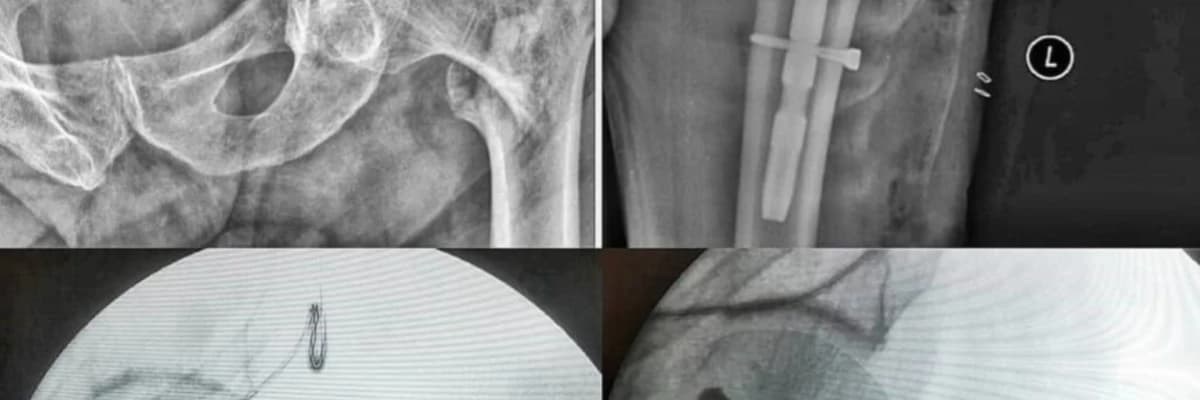

OSTEOPOROZA ( KEMİK ERİMESİ) BAĞLI KALÇA KIRIKLARI

Yaşlılardaki kalça kırıkları yaşam süresinin artması ile birlikte oldukça çok gördüğümüz bir sağlık sorunu haline gelmiştir. Kemik erimesi bulunan yaşlılarda boy mesafesinden basit düşmelerle bu kırıklar meydana gelebilmektedir. Kalça kırıklarının tedavisi cerrahidir. Tedavinin amacı hastalara tekrar ağrısız bir kalça eklemi kazandırmak, kırık öncesi günlük aktivitelere bir an önce dönüşü sağlamaktır. Eğer varsa eşlik eden kronik hastalıklar ameliyat öncesi ilgili branşlarla konsültasyonlar yapılarak gerekli hazırlıklar tamamlanmalı ve mümkünse ilk 72 saatte operasyon gerçekleştirilmelidir.